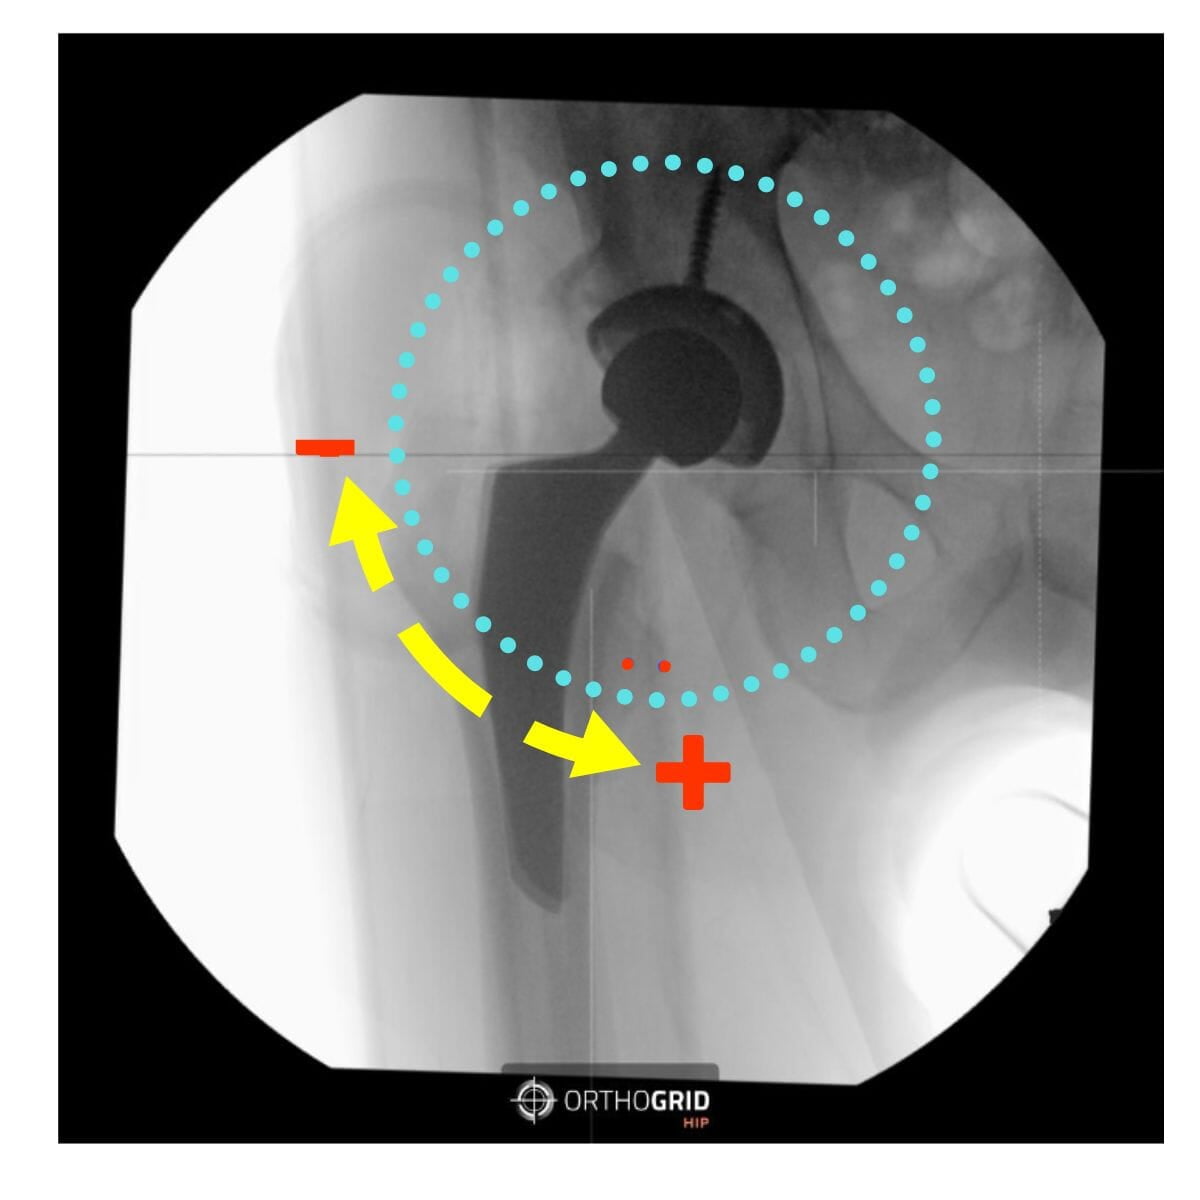

- If your cup is not in the center of the image, the cup measurement can be influenced by parallax. You'll see the Hip AI warning message. Retake image and center the Cup while keeping both Teardrops in view to Keep the Pelvis Tracking